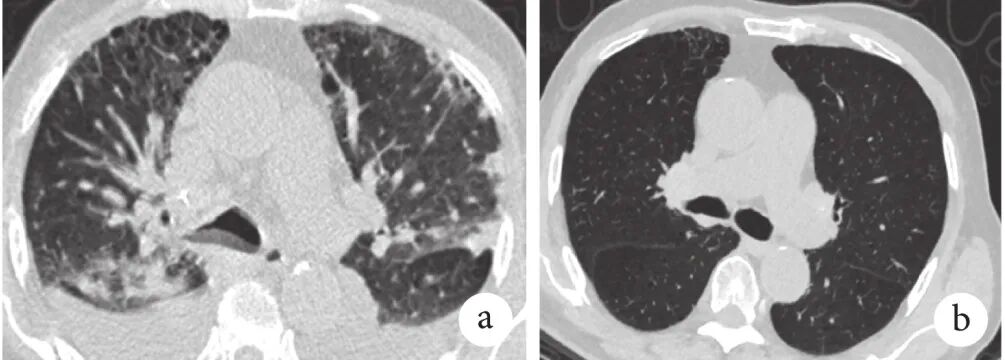

患者5,男,58岁,无吸烟史,婴儿时期曾患“麻疹性肺炎”,30余年前出现阵发性咳嗽、咳痰,诊断为“支扩”,5年前诊断“Ⅱ型呼吸衰竭”,使用ICS+LABA+LAMA及无创呼吸机辅助通气,仍有频繁急性加重。11年前查血清IgE 2456 IU/mL,10年前痰培养多次见烟曲霉。4年前再次因急性加重入院,血清IgE 568.6 IU/mL,烟曲霉特异性IgE 16 kUA/L,烟曲霉特异性IgG(+),胸部HRCT示双肺多发囊性支扩,管壁增厚,肺气肿,肺大疱(图3),诊断为ABPA,给予泼尼松联合伊曲康唑治疗,症状好转,急性加重次数减少,现维持泼尼松10 mg、1次/d,1个月前复查血清IgE 45.49 IU/mL。

图3 患者5的HRCT检查像

2019年7月5日,双肺多发支扩,其内可见黏液栓,双肺多发肺气肿、肺大疱,双侧胸膜增厚伴钙化。